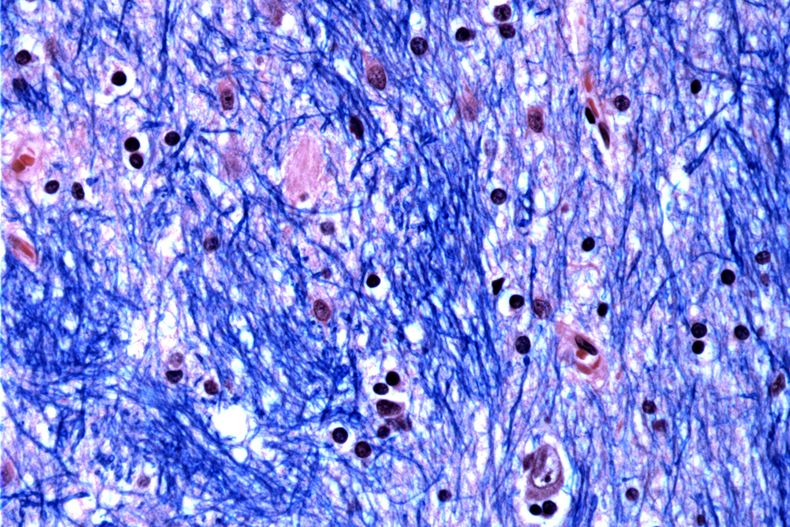

Los científicos están desentrañando el misterio de qué desencadena la enfermedad de Huntington, un trastorno hereditario devastador y mortal que aparece en la plenitud de la vida, provocando la descomposición y muerte de células nerviosas en partes del cerebro.

La muerte de las células cerebrales eventualmente conduce a problemas con el movimiento, el pensamiento y el comportamiento. Los síntomas de Huntington, que incluyen movimiento involuntario, marcha inestable, cambios de personalidad y juicio deteriorado, comienzan típicamente entre los 30 y 50 años, empeorando gradualmente durante 10 a 25 años.

Científicos del Broad Institute de MIT y Harvard, el Hospital McLean en Massachusetts y la Facultad de Medicina de Harvard estudiaron tejido cerebral donado por 53 personas con Huntington y 50 sin ella, analizando medio millón de células.

Se centraron en la mutación de Huntington, que involucra un tramo de ADN en un gen particular donde una secuencia de tres letras, CAG, se repite al menos 40 veces. En personas sin la enfermedad, esta secuencia se repite sólo de 15 a 35 veces. Descubrieron que los tramos de ADN con 40 o más “repeticiones” se expanden con el tiempo hasta que tienen cientos de CAGs. Una vez que los CAGs alcanzan un umbral de aproximadamente 150, ciertos tipos de neuronas enferman y mueren.